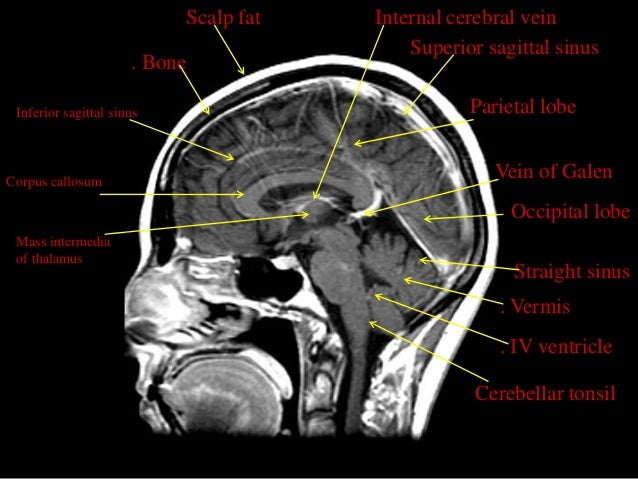

Prescribing sagittal images. Images are obtained no more than 10° oblique to a perpendicular to a line connecting the ...